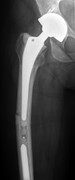

How to salvage a salvage endoprosthesis

Anil Haldar and others

Journal of Surgical Case Reports, Volume 2016, Issue 1, January 2016, rjv172, https://doi.org/10.1093/jscr/rjv172